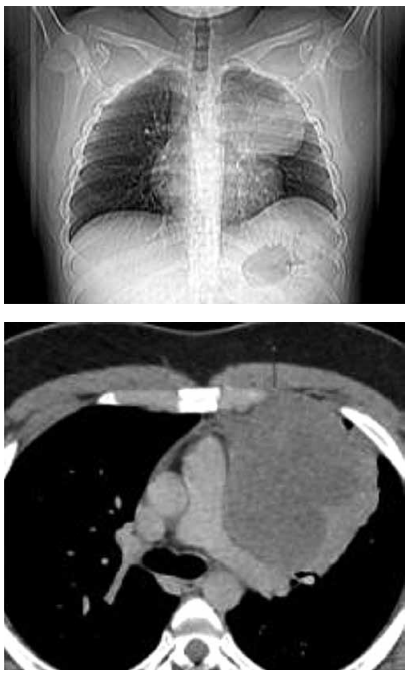

Paciente de 19 anos procura unidade básica de saúde

com queixa de dor em região anterior de hemitórax

esquerdo. Fez radiografia e tomografia, apresentadas a

seguir. Foi submetido a biópsia transtorácica, que revelou

neoplasia maligna com padrão morfológico de pequenas

células redondas e azuis (HE).

(Arquivo pessoal; imagem usada com autorização)